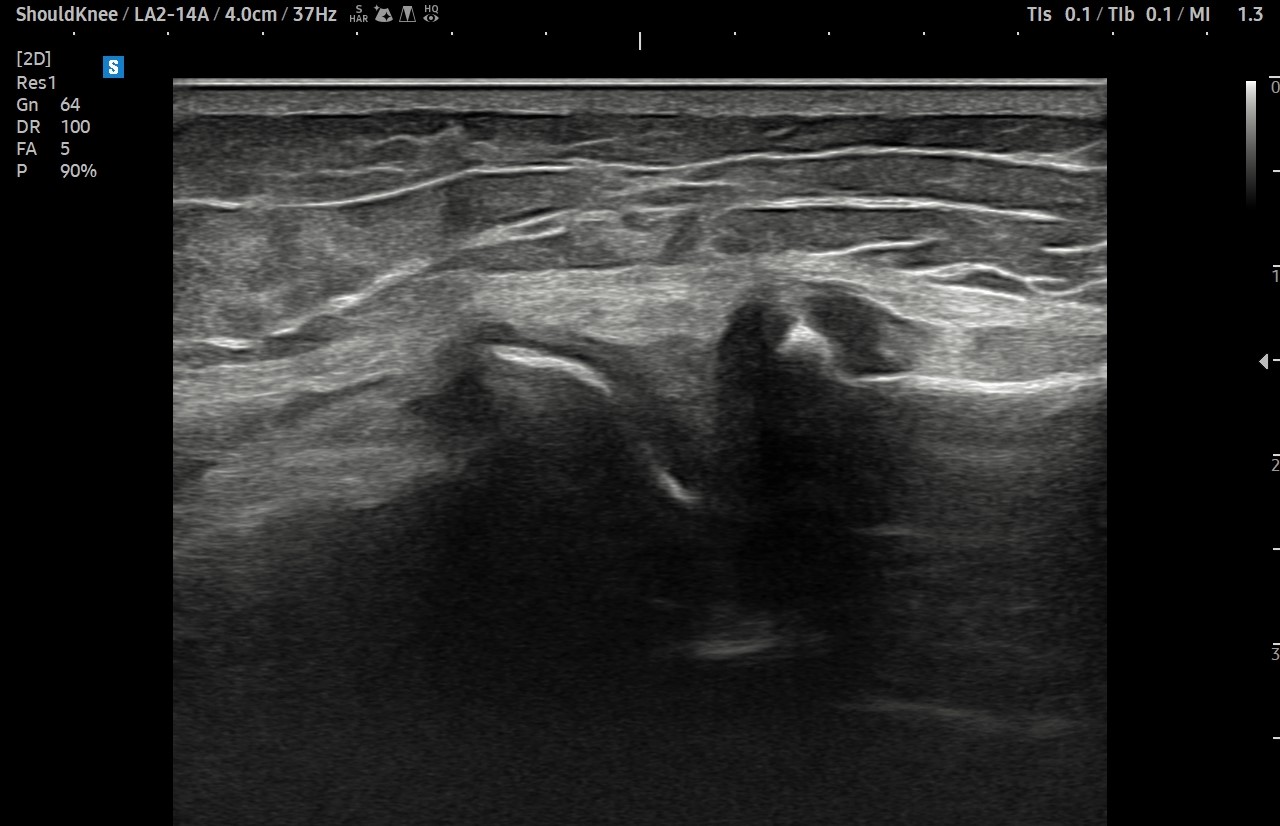

- 치료기간 : 25 . 7 . 25 ~ 25 . 9 . 3

- 치료횟수 : 5 회 (1Cycle)